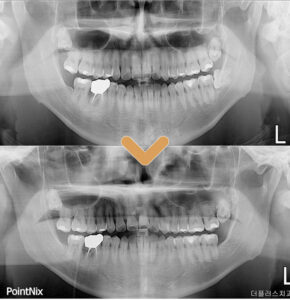

환자분의 경우처럼 수평적으로

매복되어 있는 사랑니를 발치하기 위해서는

잇몸을 절개하여 박리한 후

치아를 쪼개어 발치하게 되는데

이때 신경관이 손상 받지 않는 것이

무엇보다 중요합니다.

환자분의 발치 후 사진을 보시게 되면

신경관 손상과 부작용 없이

깔끔히 뿌리까지 발치된 모습을 보실 수 있습니다.